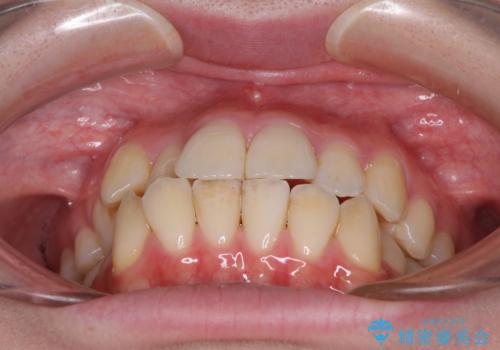

【モニター】前歯の前突感とクロスバイトをインビザラインで改善

- 前歯の突出感とクロスバイトが気になり、インビザラインによる矯正治療を希望して来院された患者様です。

上顎側切歯(上の真ん中から2番目の歯)が舌側転位している場合、インビザラインでは仕上げきれないことが多く、更には無理して動かそうとすると歯髄壊死を起こすリスクが高いと言われています。

インビザラインで歯列を移動する前に、上顎前歯をワイヤー矯正で整え、その後上下歯列をインビザラインにて矯正治療を行うこととしました。

舌側転位している側切歯特有の、切縁の位置が不揃いであったり、根元が内側に引っ込んだ状態であったりという、インビザライン独特の仕上がりになることなく、きれいに整った歯列とすることができました。